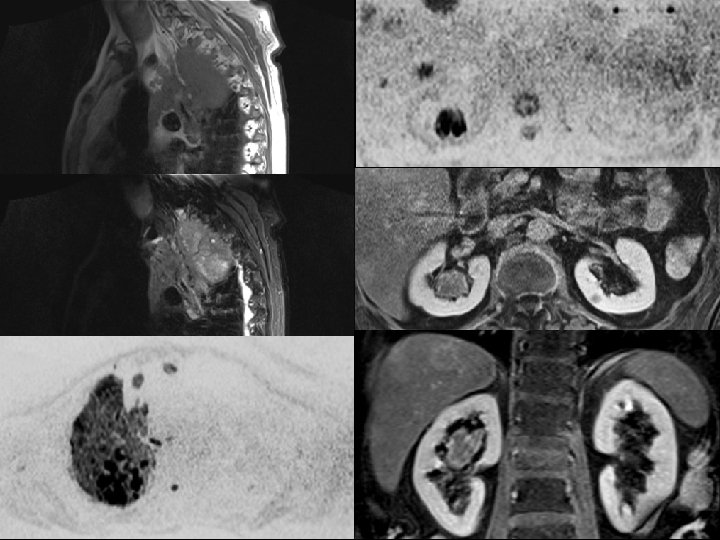

Spécificité : Actif vs résiduel Myélome multiple : Suspicion de rechute 27 ADC = 0, 783. 10 -3 2 ADC = 1, 992. 10 -3 mm 2/sec

b 50 ADC Baseline After therapy

Valeur d’ADC seuil ? 29 Khoo MY, Skeletal Radiol 2011